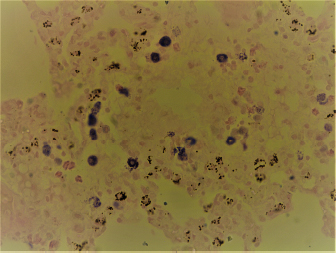

Formalin-fixed tissues were cut and processed routinely in an automatic processor for histopathological examination, according to Bancroft and Gamble (2008). Three slides were prepared from each selected tissue with 4–5 μm thickness and were stained by three different stains: Hematoxylin and Eosin stain (H&E), Wright’s stain, and toluidine blue stain. The prepared glass slides were examined blindly by a certified veterinary pathologist. In the Wright stain, the mast cells were characterized by intracytoplasmic densely basophilic granules (Fig. 1). In contrast, in the toluidine blue stain, the mast cell granules exhibited purple metachromatic granules (Fig. 2).

Fig. 2. Widespread distribution of the mast cells in the interstitium that were characterized by purple metachromatic granules in the lung of the rat (Toluidine blue stain, 40×).